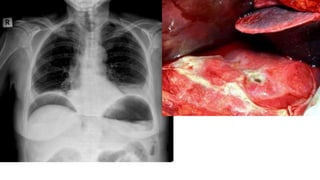

Retroperitoneal tumours

• Direct extension from surrounding Structures

• Primary tumours of mesenchymal origin

• Can be malignant ( Sarcomas)

• Liposarcoma

• Leimyosarcoma

• Malignant fibrous histiocytoma (MFH)

Retroperitoneal tumours • Directextension from surrounding Structures • Primary tumours of mesenchymal origin • Can be malignant ( Sarcomas) • Liposarcoma • Leimyosarcoma • Malignant fibrous histiocytoma (MFH)